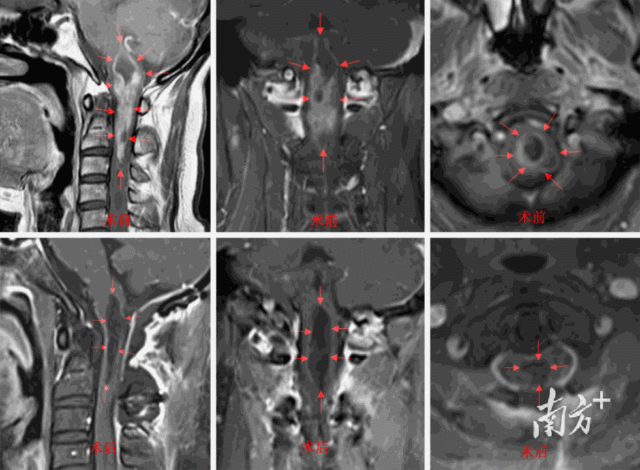

近两个月,48岁的梁阿姨出现双脚麻木症状。日前,她来到广东省人民医院(以下简称“省医”)神经外科就诊,头颅增强MR检查结果显示,她的延髓-上颈髓里长了一个长度7.2厘米的巨大肿瘤。

周德祥团队为梁阿姨仔细评估后发现,该肿瘤涉及到延髓全长及颈1-3高颈段颈髓,可能影响生命中枢、血管中枢、觉醒功能、后组颅神经功能、肢体运动感觉等重要功能。手术切除时,如果不慎损伤到瘤周重要神经组织,则可能出现术中心跳骤停,以及术后呼吸心跳停止、昏迷、高位截瘫等严重并发症。

经过6小时奋战,梁阿姨的肿瘤被完整切除,瘤周重要结构也都保存完好。术后第三天,梁阿姨脱离呼吸机,能自己呼吸及进食,无吞咽困难、饮水呛咳,肢体活动自如,逐渐下地行走。术后她的足部麻木症状也有明显好转,没有新增手术并发症。